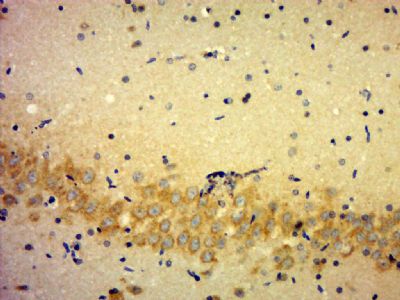

| 产品图片 | ![]() Sample: U251 (human)cell Lysate at 40 ug Primary: Anti-KLHDC7B(bs-16761R) at 1/300 dilution Secondary: IRDye800CW Goat Anti-Rabbit IgG at 1/20000 dilution Predicted band size: 63 kD Observed band size: 63 kD ![]() Paraformaldehyde-fixed, paraffin embedded (Rat brain); Antigen retrieval by boiling in sodium citrate buffer (pH6.0) for 15min; Block endogenous peroxidase by 3% hydrogen peroxide for 20 minutes; Blocking buffer (normal goat serum) at 37°C for 30min; Antibody incubation with (KLHDC7B) Polyclonal Antibody, Unconjugated (bs-16761R) at 1:500 overnight at 4°C, followed by a conjugated secondary (sp-0023) for 20 minutes and DAB staining. |